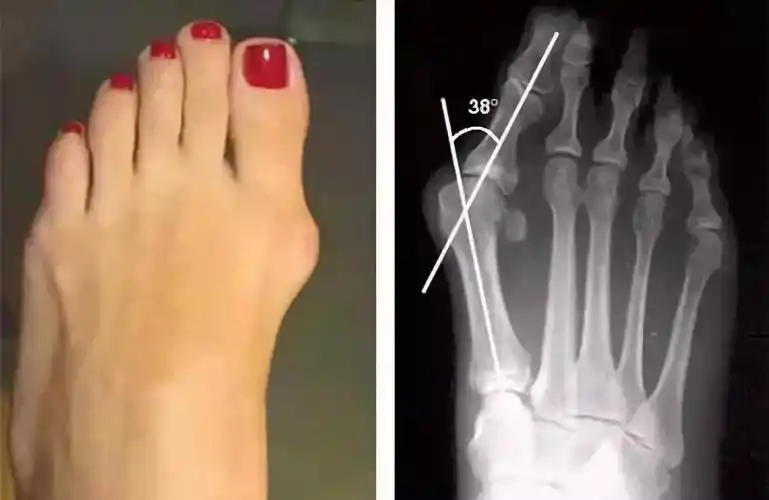

拇外翻

拇外翻是指拇趾在第一跖趾关节处向外偏斜超过正常生理范围的一种前足